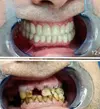

Zirkonyum uygulamalar

Porselen uygulamaları

Laminate veneer